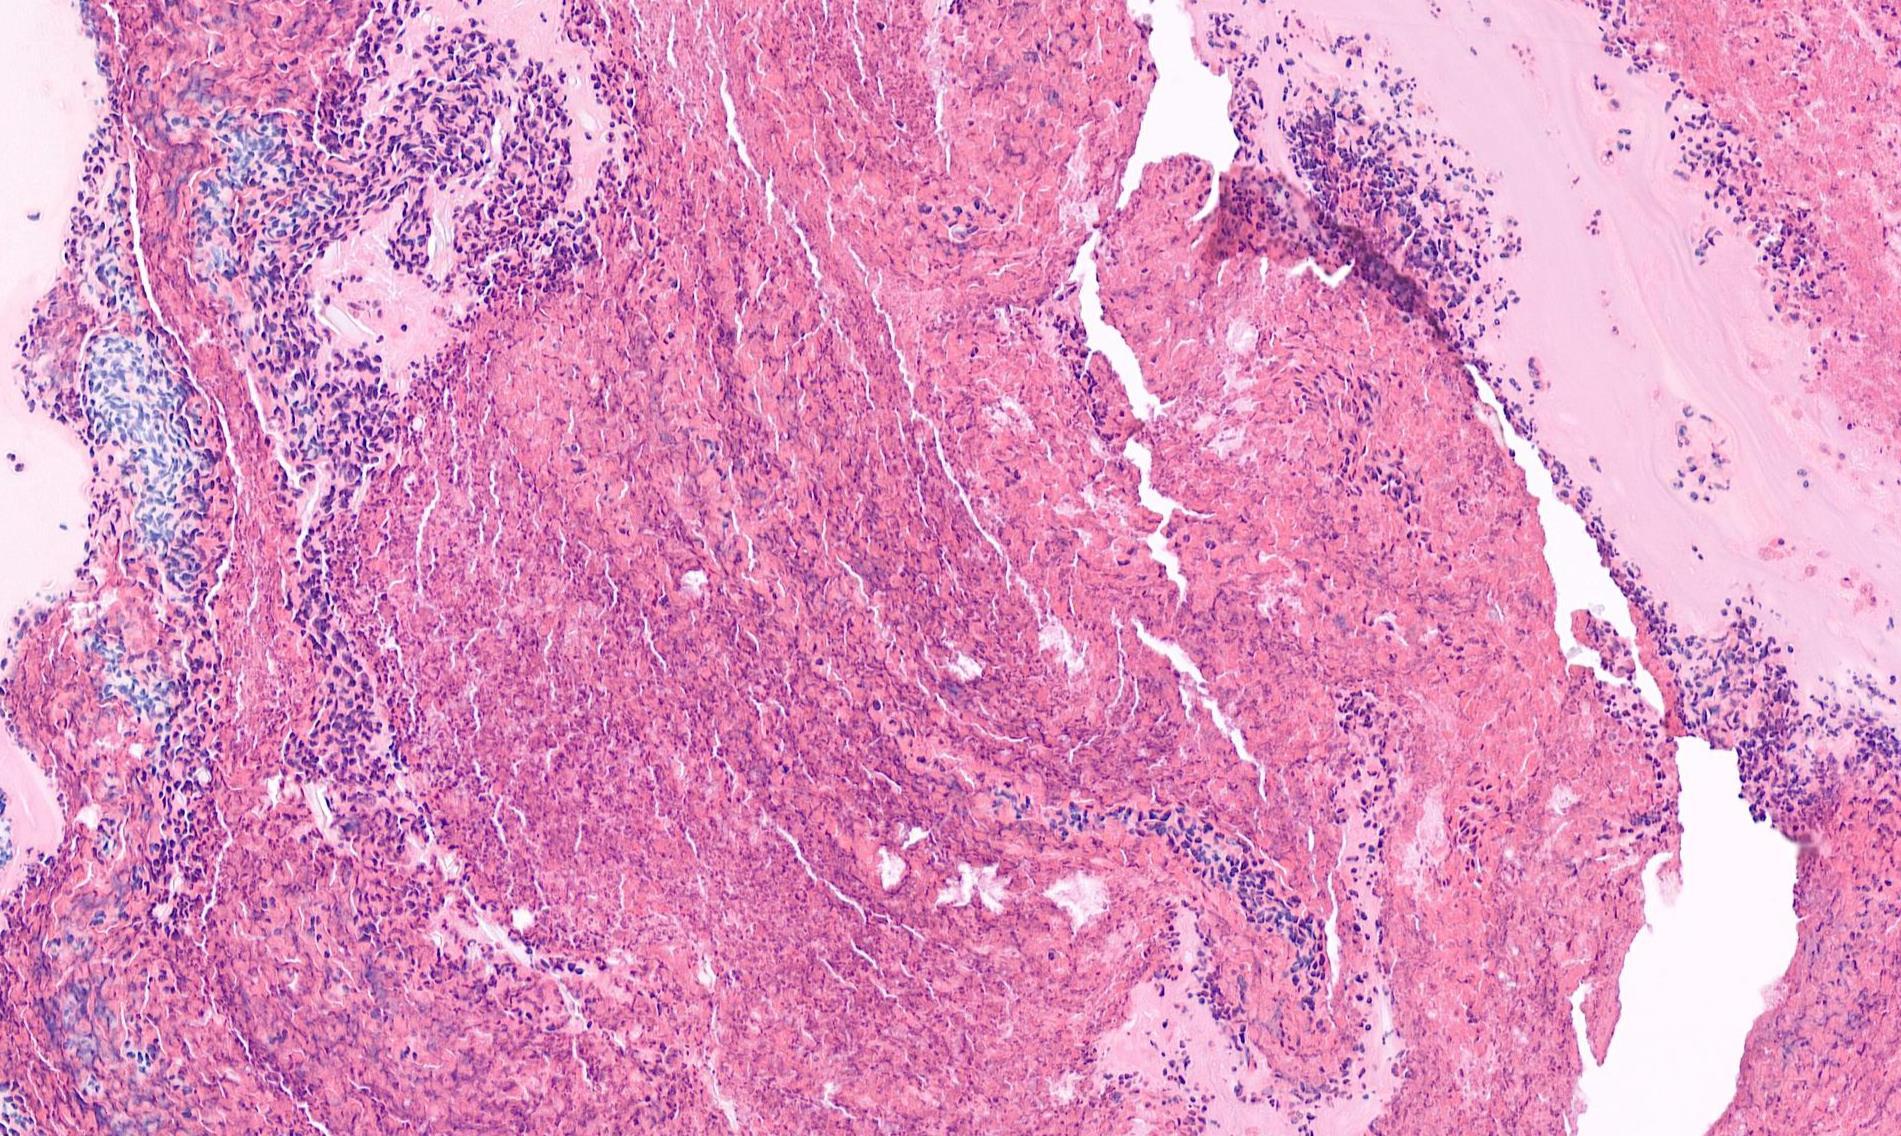

Case 2- Salient points • Multicystic and solid • Epidermoid, clear cells and mucous cells • Low grade- predominantly cystic • Work up? ABPAS, DPAS • CK7, P63 • Molecular: translocation at t(11;19)(q21;p13) expressing CRTC1::MAML2 fusion gene • DD-papillary cystadenoma, mucous retention cyst

Mucoepidermoid carcinoma, low grade

MEC Grading

commonest grading system:

-Intracystic component <20% -Neural invasion -Necrosis -Mitoses >4/10 hpf -Ananplasia